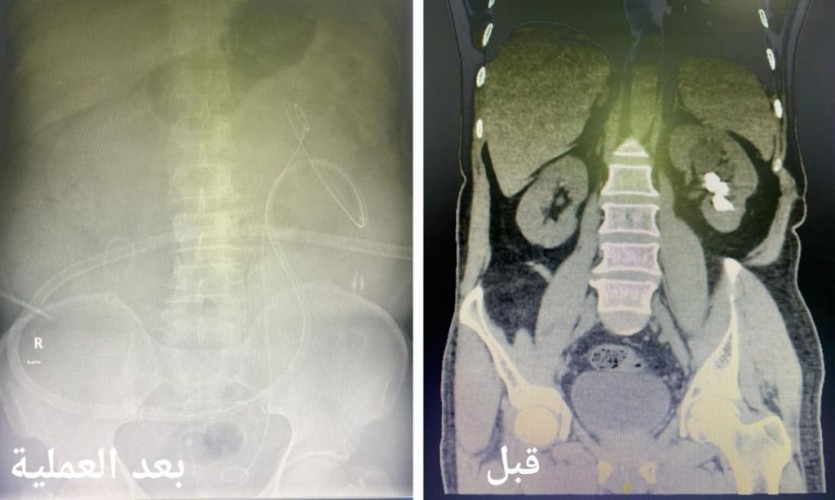

وأكدت أن الآم إزدادت خلال الأشهر الأخيرة مع المريض مع وجود تاريخ مرضي قديم يؤكد وجود حصوات في الجهاز البولي تسببت له تلك الاعراض مما استدعى سرعة إستكمال الفحوصات الطبية اللازمة والفحوص المخبرية للدم و البول و الفحوص الإشعاعية التصويرية بالأشعة المقطعية تبين خلالها وجود حصوات في حوض و تجويف الكلية اليسرى بحجم 3 سنتيمتر .

وأضحت أنه تم تجهيز المريض ونقله لغرفة العمليات وعمل تدخل جراحي كلوي دقيق بشق سنتيمتر واحد في الجلد بإستخدام التقنيات الطبية الحديثة لإستئصال الحصوات في جلسة جراحية واحدة و إزالتها بالكامل بواسطة ( المنظار الجلدي الكلوي ) و جهاز التيليسكوب و أدوات طبية صغيرة الحجم حيث تم إغلاق الشق الجراحي بخياطة واحدة دون حدوث أي مضاعفات ولله الحمد